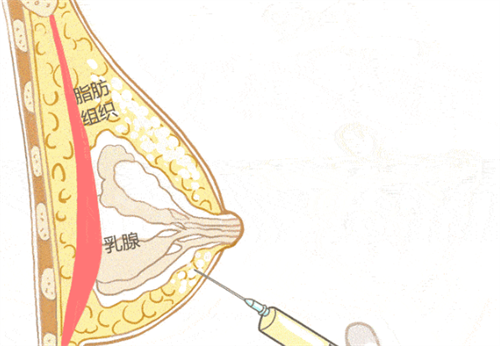

胸部注射物取出+假体植入:52000元起